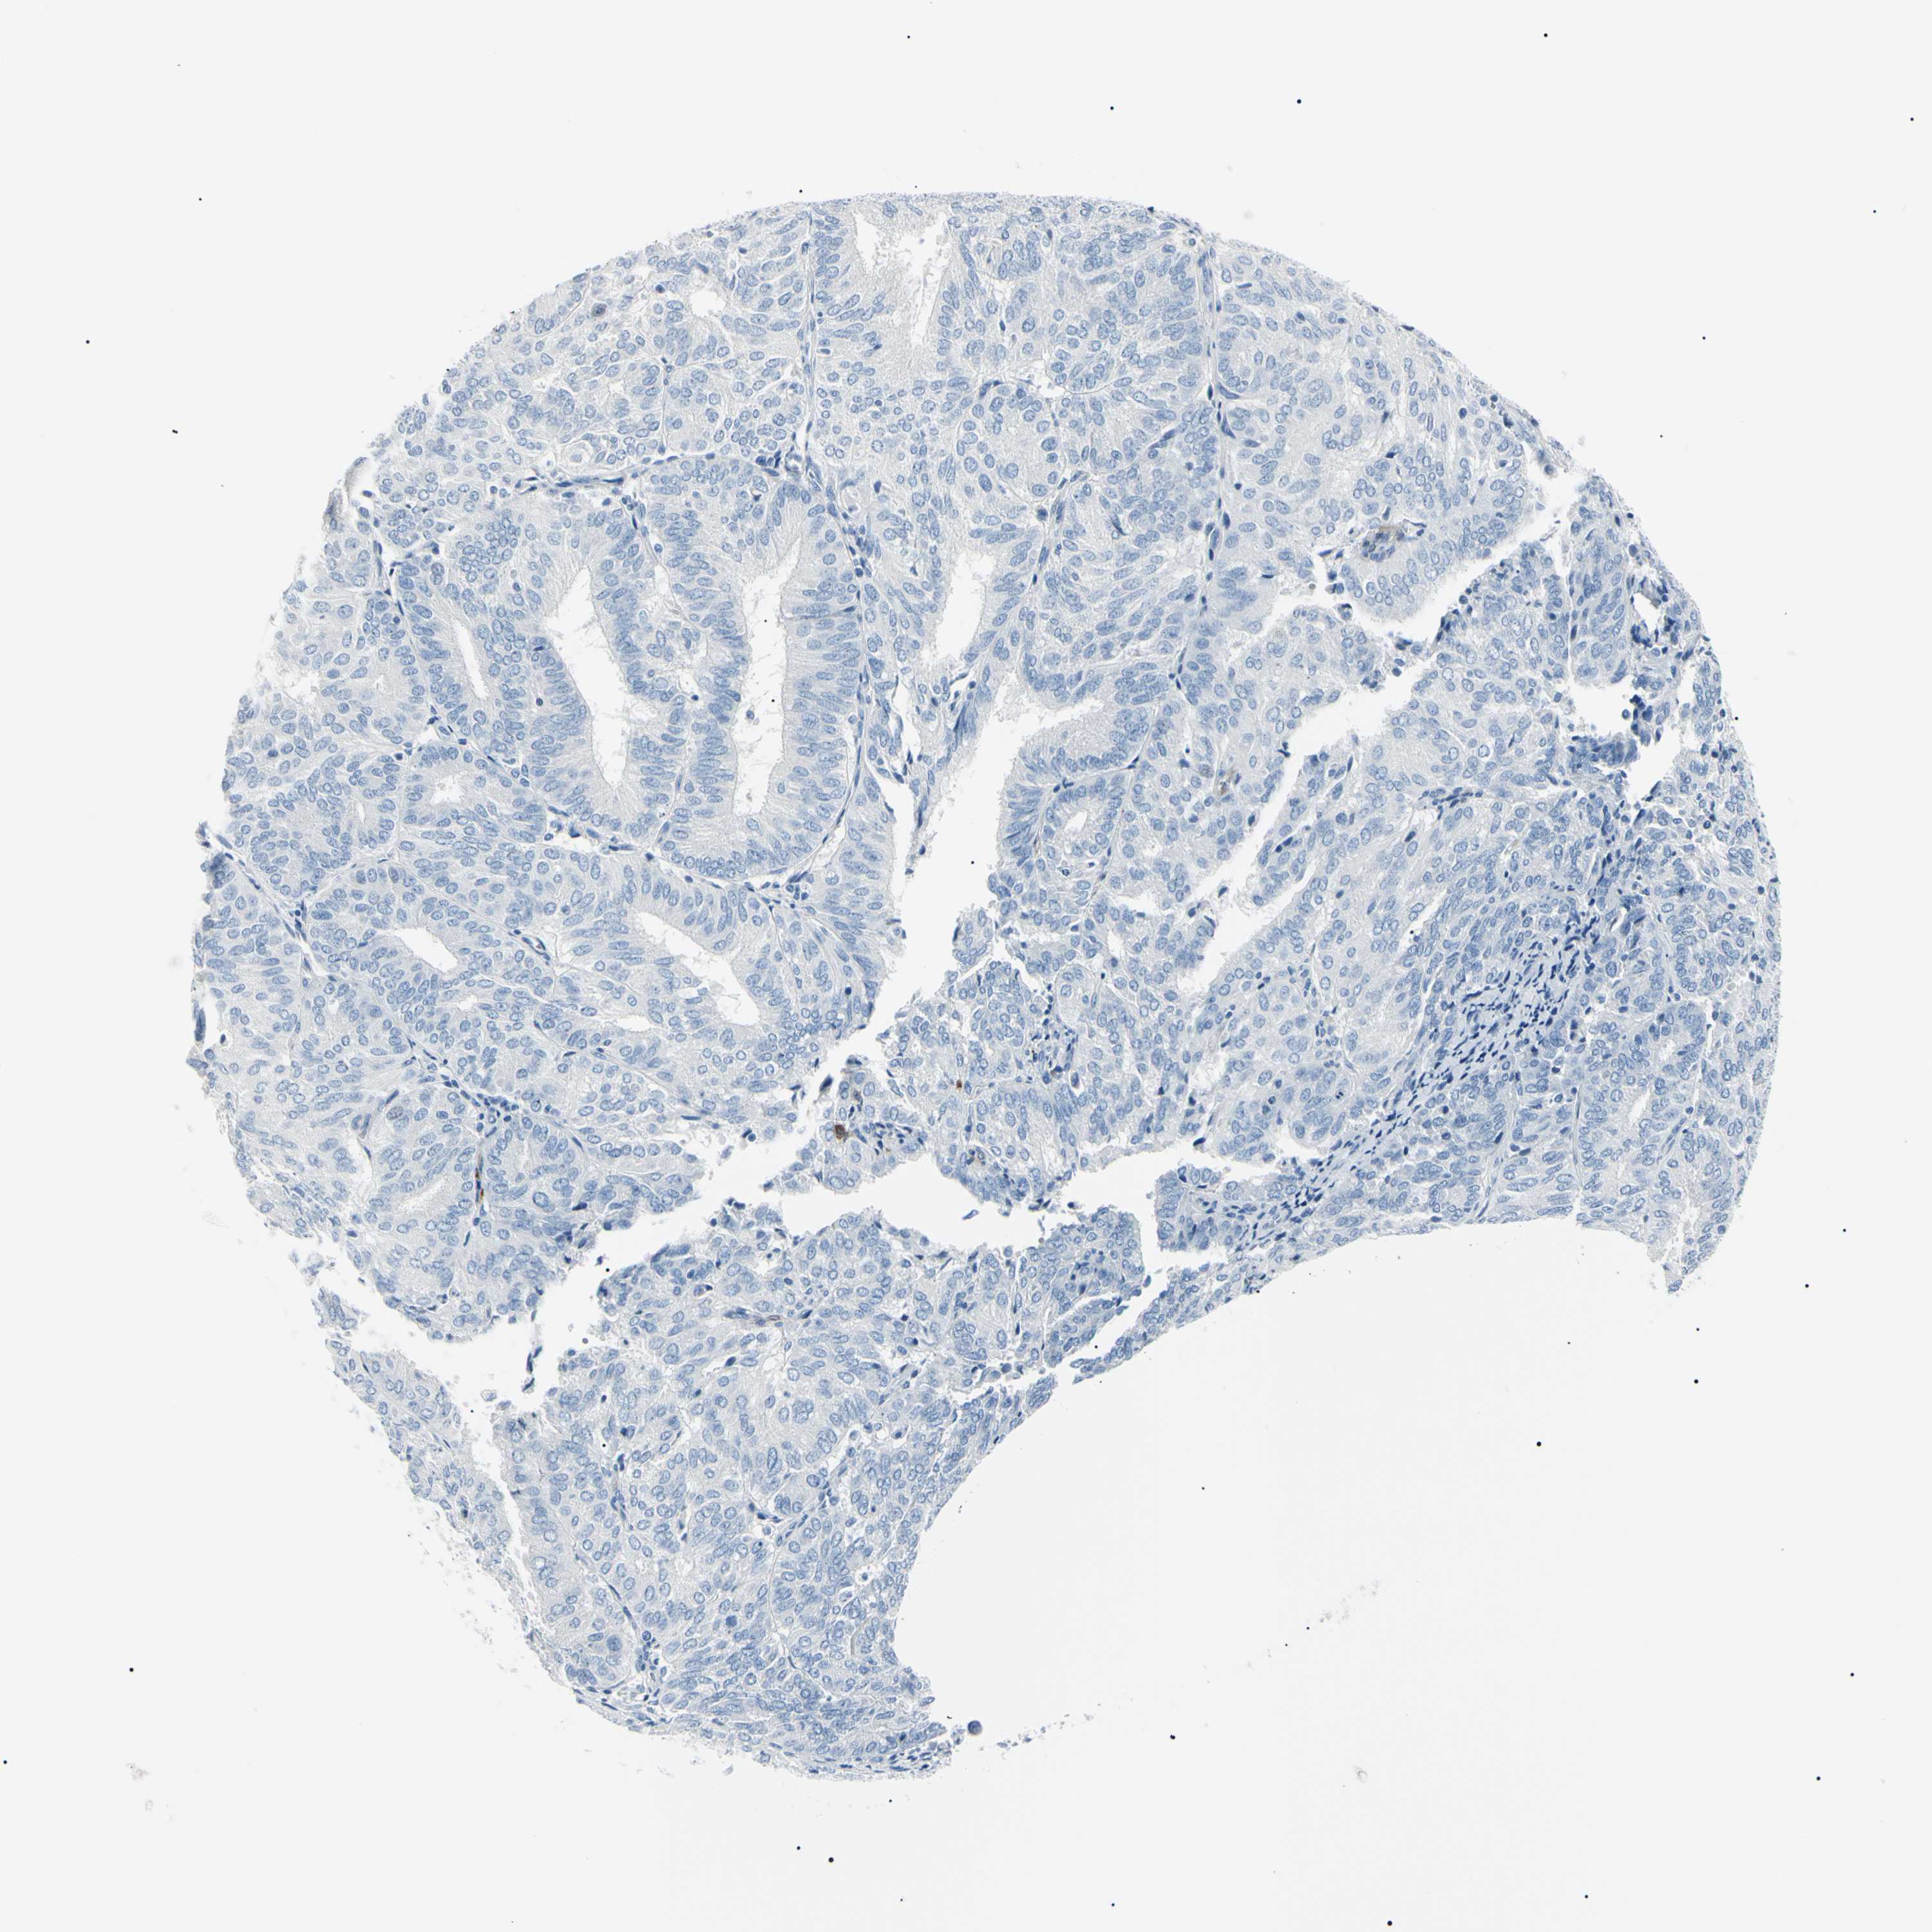

ENDOMETRIAL CANCER - Protein expressioni

A mouse-over function shows sample information and annotation data. Click on an image to view it in a full screen mode. Samples can be filtered based on level of antibody staining by selecting one or several of the following categories: high, medium, low and not detected. The assay and annotation is described here.

Note that samples used for immunohistochemistry by the Human Protein Atlas do not correspond to samples in the TCGA dataset.

Antibody stainingi

Antibody staining in the annotated cell types in the current human tissue is reported as not detected, low, medium, or high, based on conventional immunohistochemistry profiling in selected tissues. This score is based on the combination of the staining intensity and fraction of stained cells.

Each image is clickable and will lead to virtual microscopy that enables deeper exploration of all samples and also displays staining intensity scores, fraction scores and subcellular localization as well as patient and tissue information for each sample.

Antibody HPA001550

Antibody CAB010102

Staining

High

Medium

Low

Not detected

Intensity

Strong

Moderate

Weak

Negative

Quantity

>75%

75%-25%

<25%

None

Location

Nuclear

Cytoplasmic/membranous

Cytoplasmic/membranous,nuclear

Adenocarcinoma, NOS